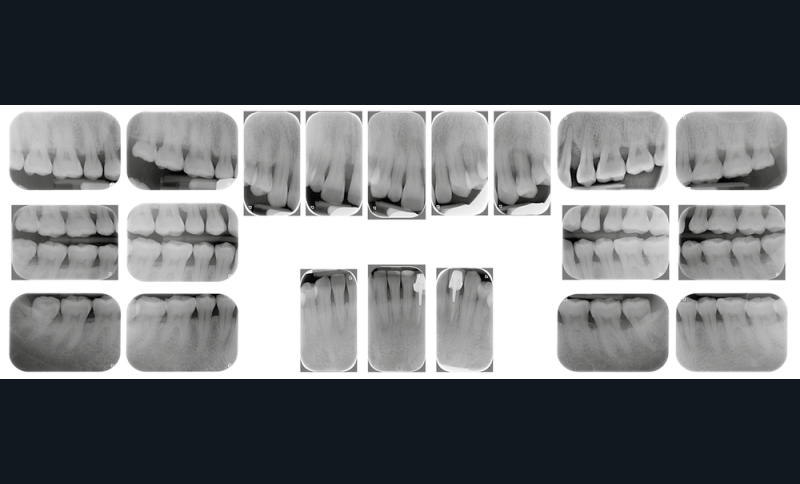

À l’examen clinique et radiologique, elle présente une parodontite de stade 4 grade C avec des poches profondes au niveau des dents 11 et 24, associées à des alvéolyses angulaires atteignant la moitié ou les deux tiers de la hauteur radiculaire au niveau du secteur incisivo-canin maxillaire, et le quart de la longueur radiculaire des premières molaires maxillaires et mandibulaires (fig. 2).